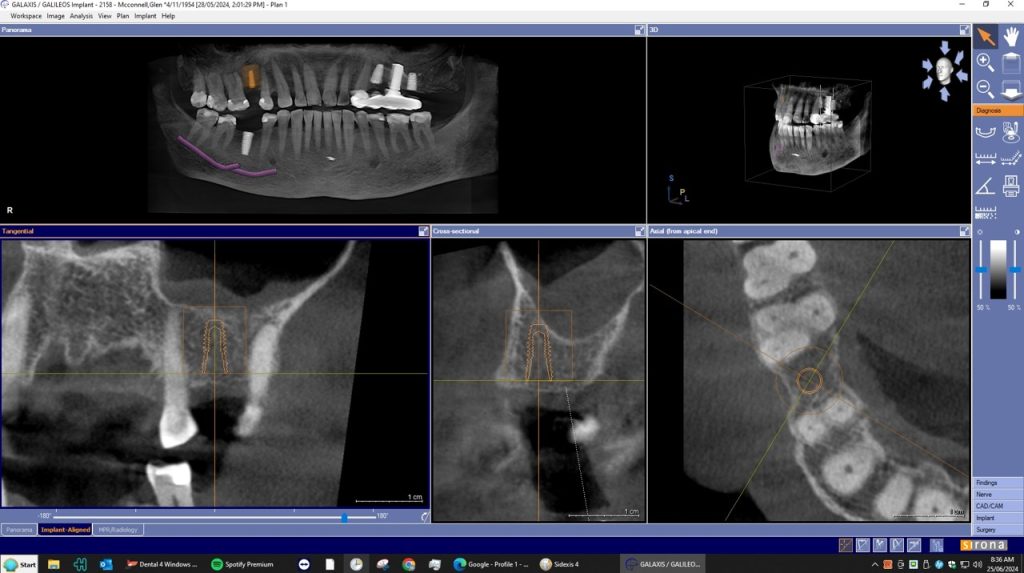

A dental Implant is a titanium “root” that integrates directly with the surrounding bone and replaces the function of the natural tooth. Neoss Implants are made using the best quality medical grade titanium, which is well known for its proven biocompatibility, and have a treated surface to facilitate bone integration.